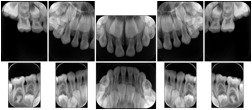

3. A dental provider wishes to capture a series of DICOM IO images for the patient’s dentition. The tooth morphology, teeth are divided into molars, premolars, canines and incisors, and a number of images for each jaw. The anatomic information was captured utilizing the triplet of schema. This standard code sequence is based on ISO 3950-2010, Dentistry - Designation system for teeth and areas of the oral cavity.

Every IO image should have anatomic information either through the primary or modifier sequence.

In most standard cases, images are oriented in structured layouts. These structured displays are useful to be shared between providers for reference purposes.

Table OO.1.1-1 shows structured display standard templates, where Viewset ID is based on the Japanese Society for Oral and Maxillofacial Radiology (JSOMR) classification provided by JIRA (Japan Medical Imaging and Radiological Systems Industries Association, www.jira-net.or.jp). Expected or typical teeth to be imaged location, region and designation codes are based on ISO 3950-2010, Dentistry - Designation system for teeth and areas of the oral cavity. For all the hanging protocols listed in OO.1.1-1, the value to use for Hanging Protocol Creator (0072,0008) is "JSOMR" and the value to use for Hanging Protocol Name (0072,0002) does not include "JSOMR" (e.g., "DL-S001A", not "JSOMR DL-S001A").